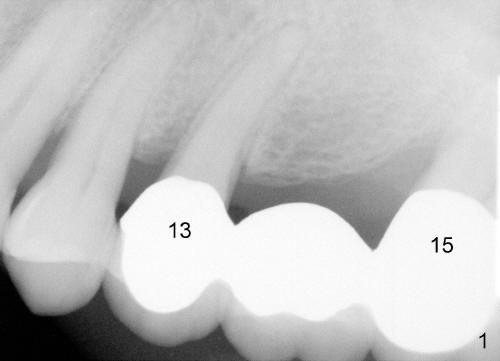

Mr. Tsang has a loose bridge (Fig.1: #13-15). The affected tooth (#15) was extracted two months ago. Immediate implant was placed (Fig.2: 4.5x17 mm tapered drill; Fig.3: 7x17 mm implant). It appears that the implant at the site of #15 must be somewhat parallel to the tooth #13, according to the trajectory of the drill in Fig.2.